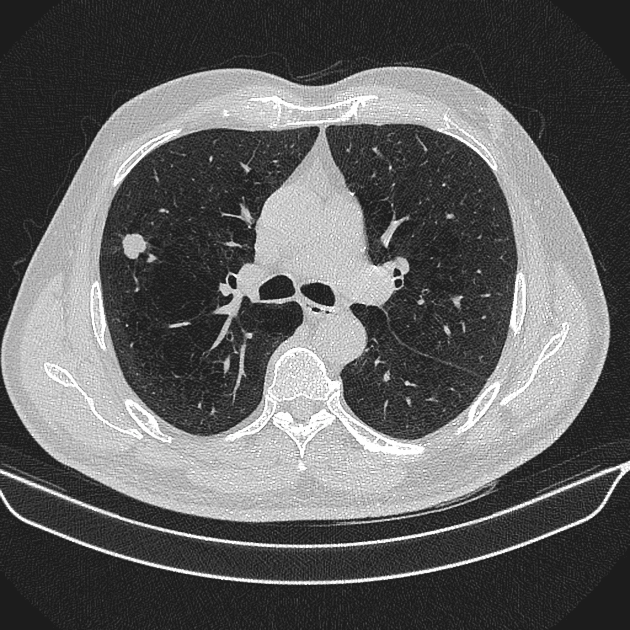

U phổi

» Thông tin: Nam giới – 70 tuổi.

» Lâm sàng: Ho / Tiền sử hút thuốc lá.

# Ung thư biểu mô tuyến (Adenocarcinoma).